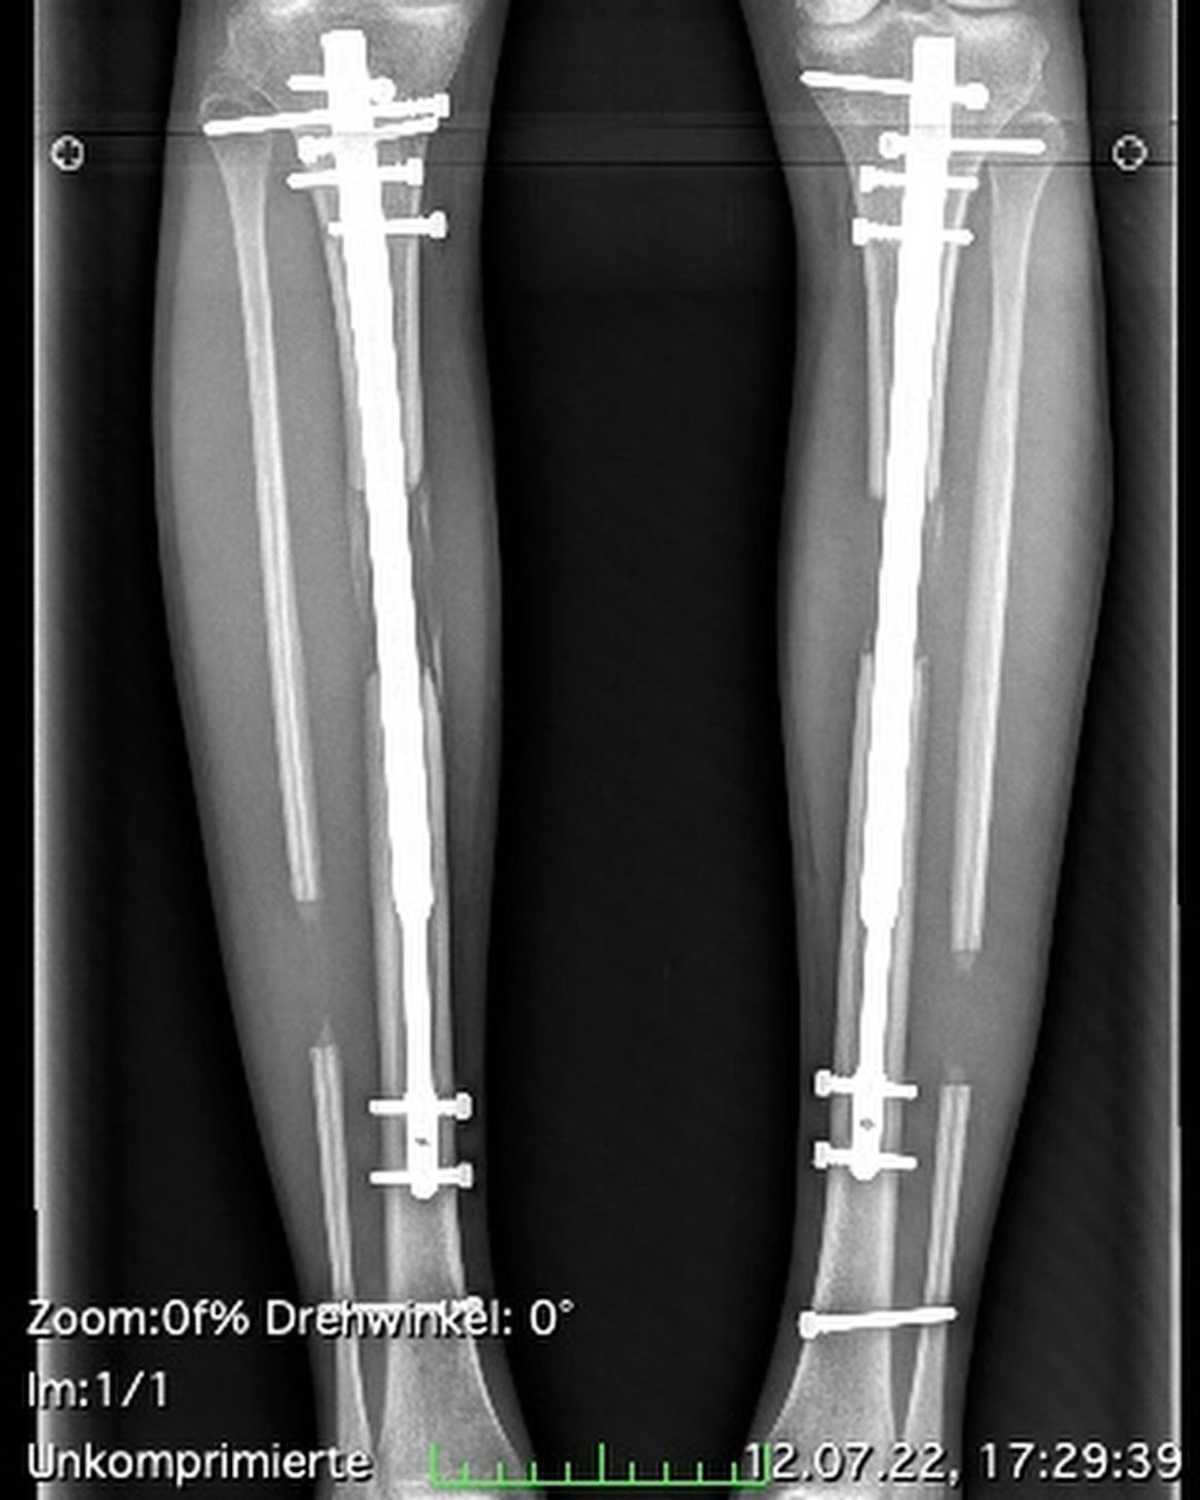

在一次次的要求下,原本對身高樣貌都非常有自信的Theresia也變得越來越懷疑自己,甚至答應Thomas的要求,豪花13萬英鎊(約120萬港元)兩度進行增高手術。2016年時進行第一次手術,利用伸縮桿加長大腿長度,足足8.5cm!而第二次手術則是在2022年的時候,進行小腿伸展手術,再加長了5.5cm,所以從原本的167一路增高到181cm的逆天長腿!

不過Theresia的增高過程也對她造成巨大的傷害,整個過程變得非常痛苦:「我的脛骨被打斷,小腿肌肉被撕裂,在裡面安裝一個可伸縮的裝置,每次使用裝置時都可以聽到哢噠哢噠的聲音」,而這些痛苦是即使吃了止痛藥也難以忍受的劇痛!